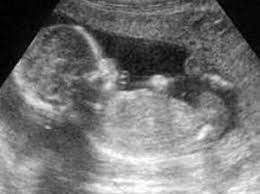

Με ειδικά μηχανήματα στέλνουμε τον ήχο (υπέρηχο) μέσα στο σώμα μας. Αν εκεί βρει σκληρό ιστό π.χ. κόκαλο, ανακλάται και δίνει στο μόνιτορ εικόνα έντονη άσπρη, αν βρει μαλακό ιστό, π.χ. υγρό δεν ανακλάται και δίνει στο μόνιτορ εικόνα μαύρη. Αναλόγως με την πυκνότητα λοιπόν, θα είναι η εικόνα στο μόνιτορ και των άλλων ιστών (ανοιχτό γκρι, σκούρο γκρι), με αποτέλεσμα να έχουμε μια εικόνα, (περίπου) των εσωτερικών μας οργάνων.

Στην μαιευτική: Την κοιλιακή την χρησιμοποιούμε για προχωρημένη εγκυμοσύνη.

Γενικά στην μαιευτική οι υπέρηχοι έχουν προσφέρει πάρα πολλά με την εξέλιξη των μηχανημάτων αυτών, ώστε με τα τρισδιάστατα (3D) και τετρασδιάστατα (4D) μηχανήματα να έχουμε εικόνα περίπου σαν την φωτογραφία του εμβρύου.

Με την εξέταση υπερήχων β'; επιπέδου, ελέγχουμε τα όργανα του εμβρύου (όσα μπορούμε) για μια σωστή ανατομία του εμβρύου. Στην εξέταση αναφέρονται σε χαρτί τα όργανα που ελέγχθηκαν. Με τον υπέρηχο μπορεί να φανεί και το φύλο του εμβρύου. Αν δεν υπήρχαν οι υπέρηχοι, δεν θα μπορούσε να γίνει η αμνιοπαρακέντηση με ασφάλεια, ούτε η λήψης τροφοβλάστης.